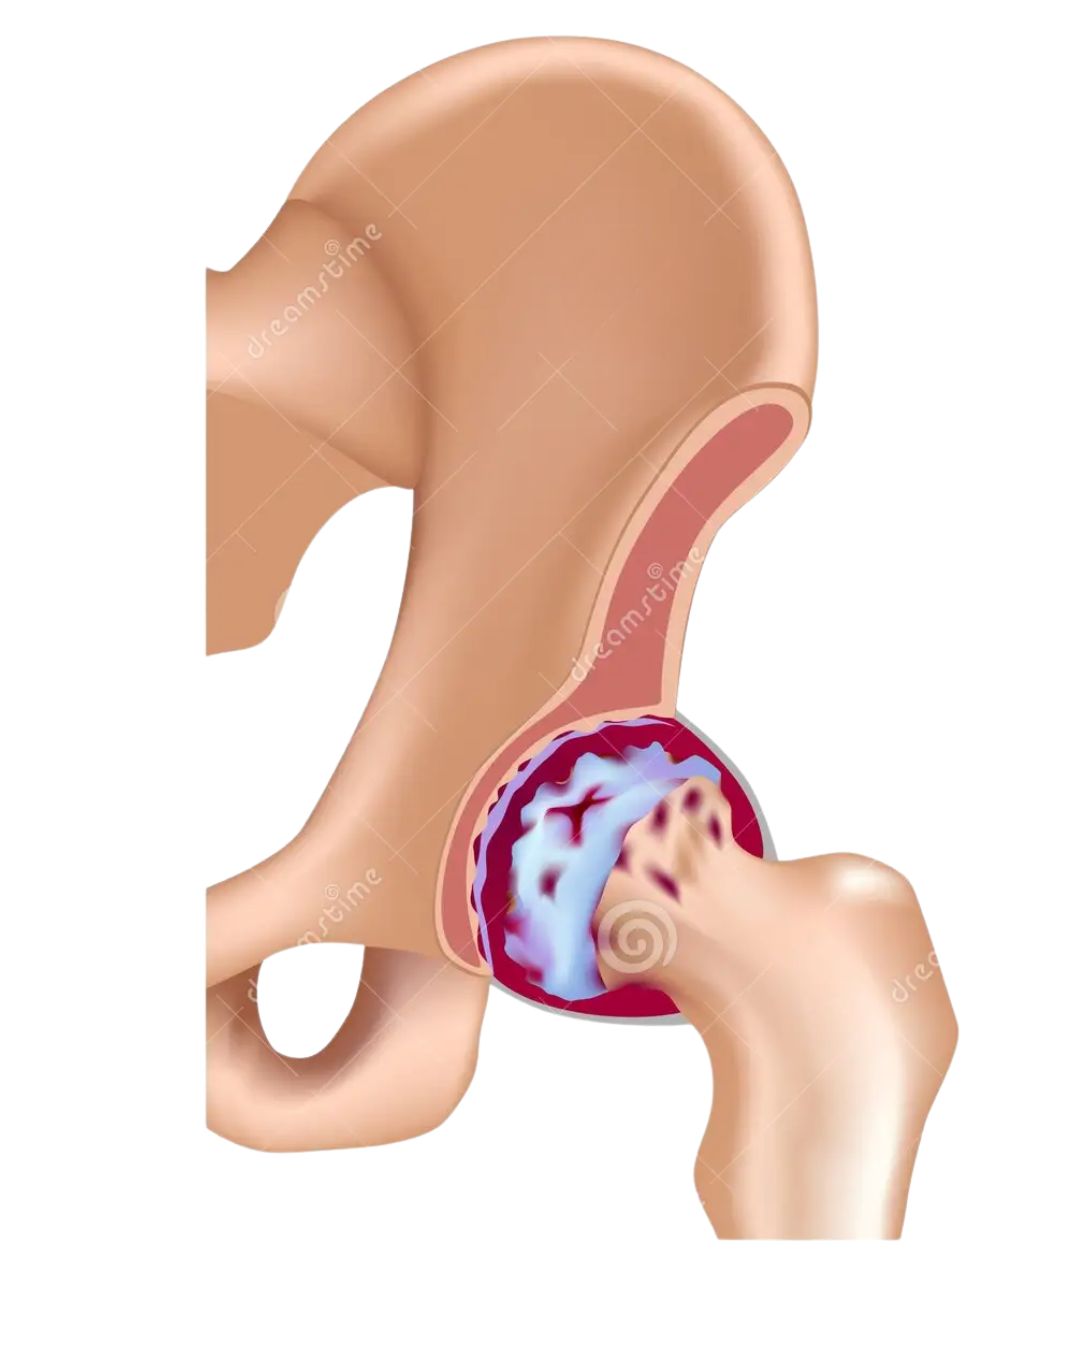

Osteoarthritis of the hip

Rheumatoid arthritis

Severe hip stiffness and deformity